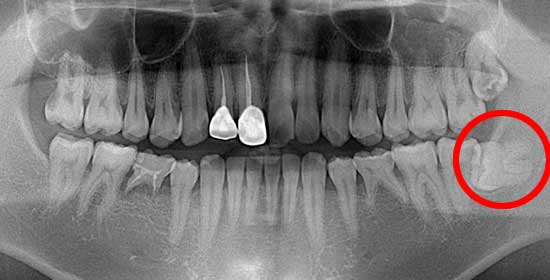

術前後のレントゲン写真

このように横に生えていると、7番目の歯と親知らずの隙間に細菌が溜まり、虫歯になったり、周囲の歯肉が腫れたりする原因となります。

術 前